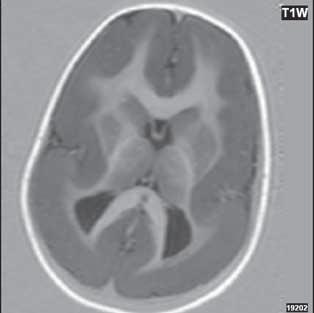

Při agenezi corpus callosum CT i MR zobrazí paralelní průběh postranních mozkových komor (oproti fyziologickému

konvergentnímu průběhu) a jejich oddálení, časté rozšíření okcipitálních rohů – colpocefalie, někdy středočárový lipom, cystu. Koronální řezy ukážou rozšíření frontálních rohů postranních komor, III. komora je situována vysoko mezi postranní komory, tvoří jakoby trojzubec, který někteří autoři přirovnávají k přilbě Vikinga. Není patrné septum pellucidum. Častá je přítomnost středočárového lipomu nebo cysty.

Na vnitřní straně postranních komor pozorujeme v T2W obrazu poněkud tmavší strukturu než okolní myelinizovaná vlákna (naopak v T1W obrazu zvýšený signál), Probstovy provazce, axony, které za fyziologických okolností přecházejí přes corpus callosum do kontralaterální hemisféry.

Sagitální řezy nám přinášejí nejvíce informací o corpus callosum. Pozorujeme radiální průběh mozkových sulků ke stropu III. komory na vnitřní straně mozkových hemisfér a naopak nezobrazíme gyrus cinguli. Při parciální agenezi je postiženo především splenium.

Obr. I.1.2a Paralelní postavení postranních komor, kolpocefalie, ageneze corpus callosum

Obr. I.1.2b Ageneze corpus callosum

Obr. I.1.2c Ageneze corpus callosum, frontální rohy postranních komor mají tvar rohů na Vikingské helmě, kraniálně uložená III komora

Obr. I.1.2d Ageneze corpus callosum, intrauterinní vyšetření (gestační stáří 23 + 5)

Obr. I.1.2e Ageneze corpus callosum, frontální rohy postranních komor mají tvar rohů na Vikingské helmě, kraniálně uložená

III komora, Probstovy provazce (šipka)